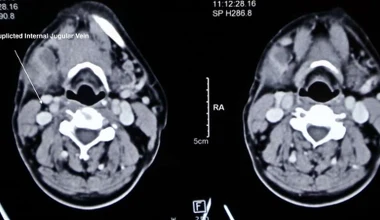

Nietypowe odkrycie podczas operacji szyi - w historii odnotowano cztery takie przypadki

Niezwykłe odkrycie podczas operacji szyi. To dopiero piąty taki przypadek